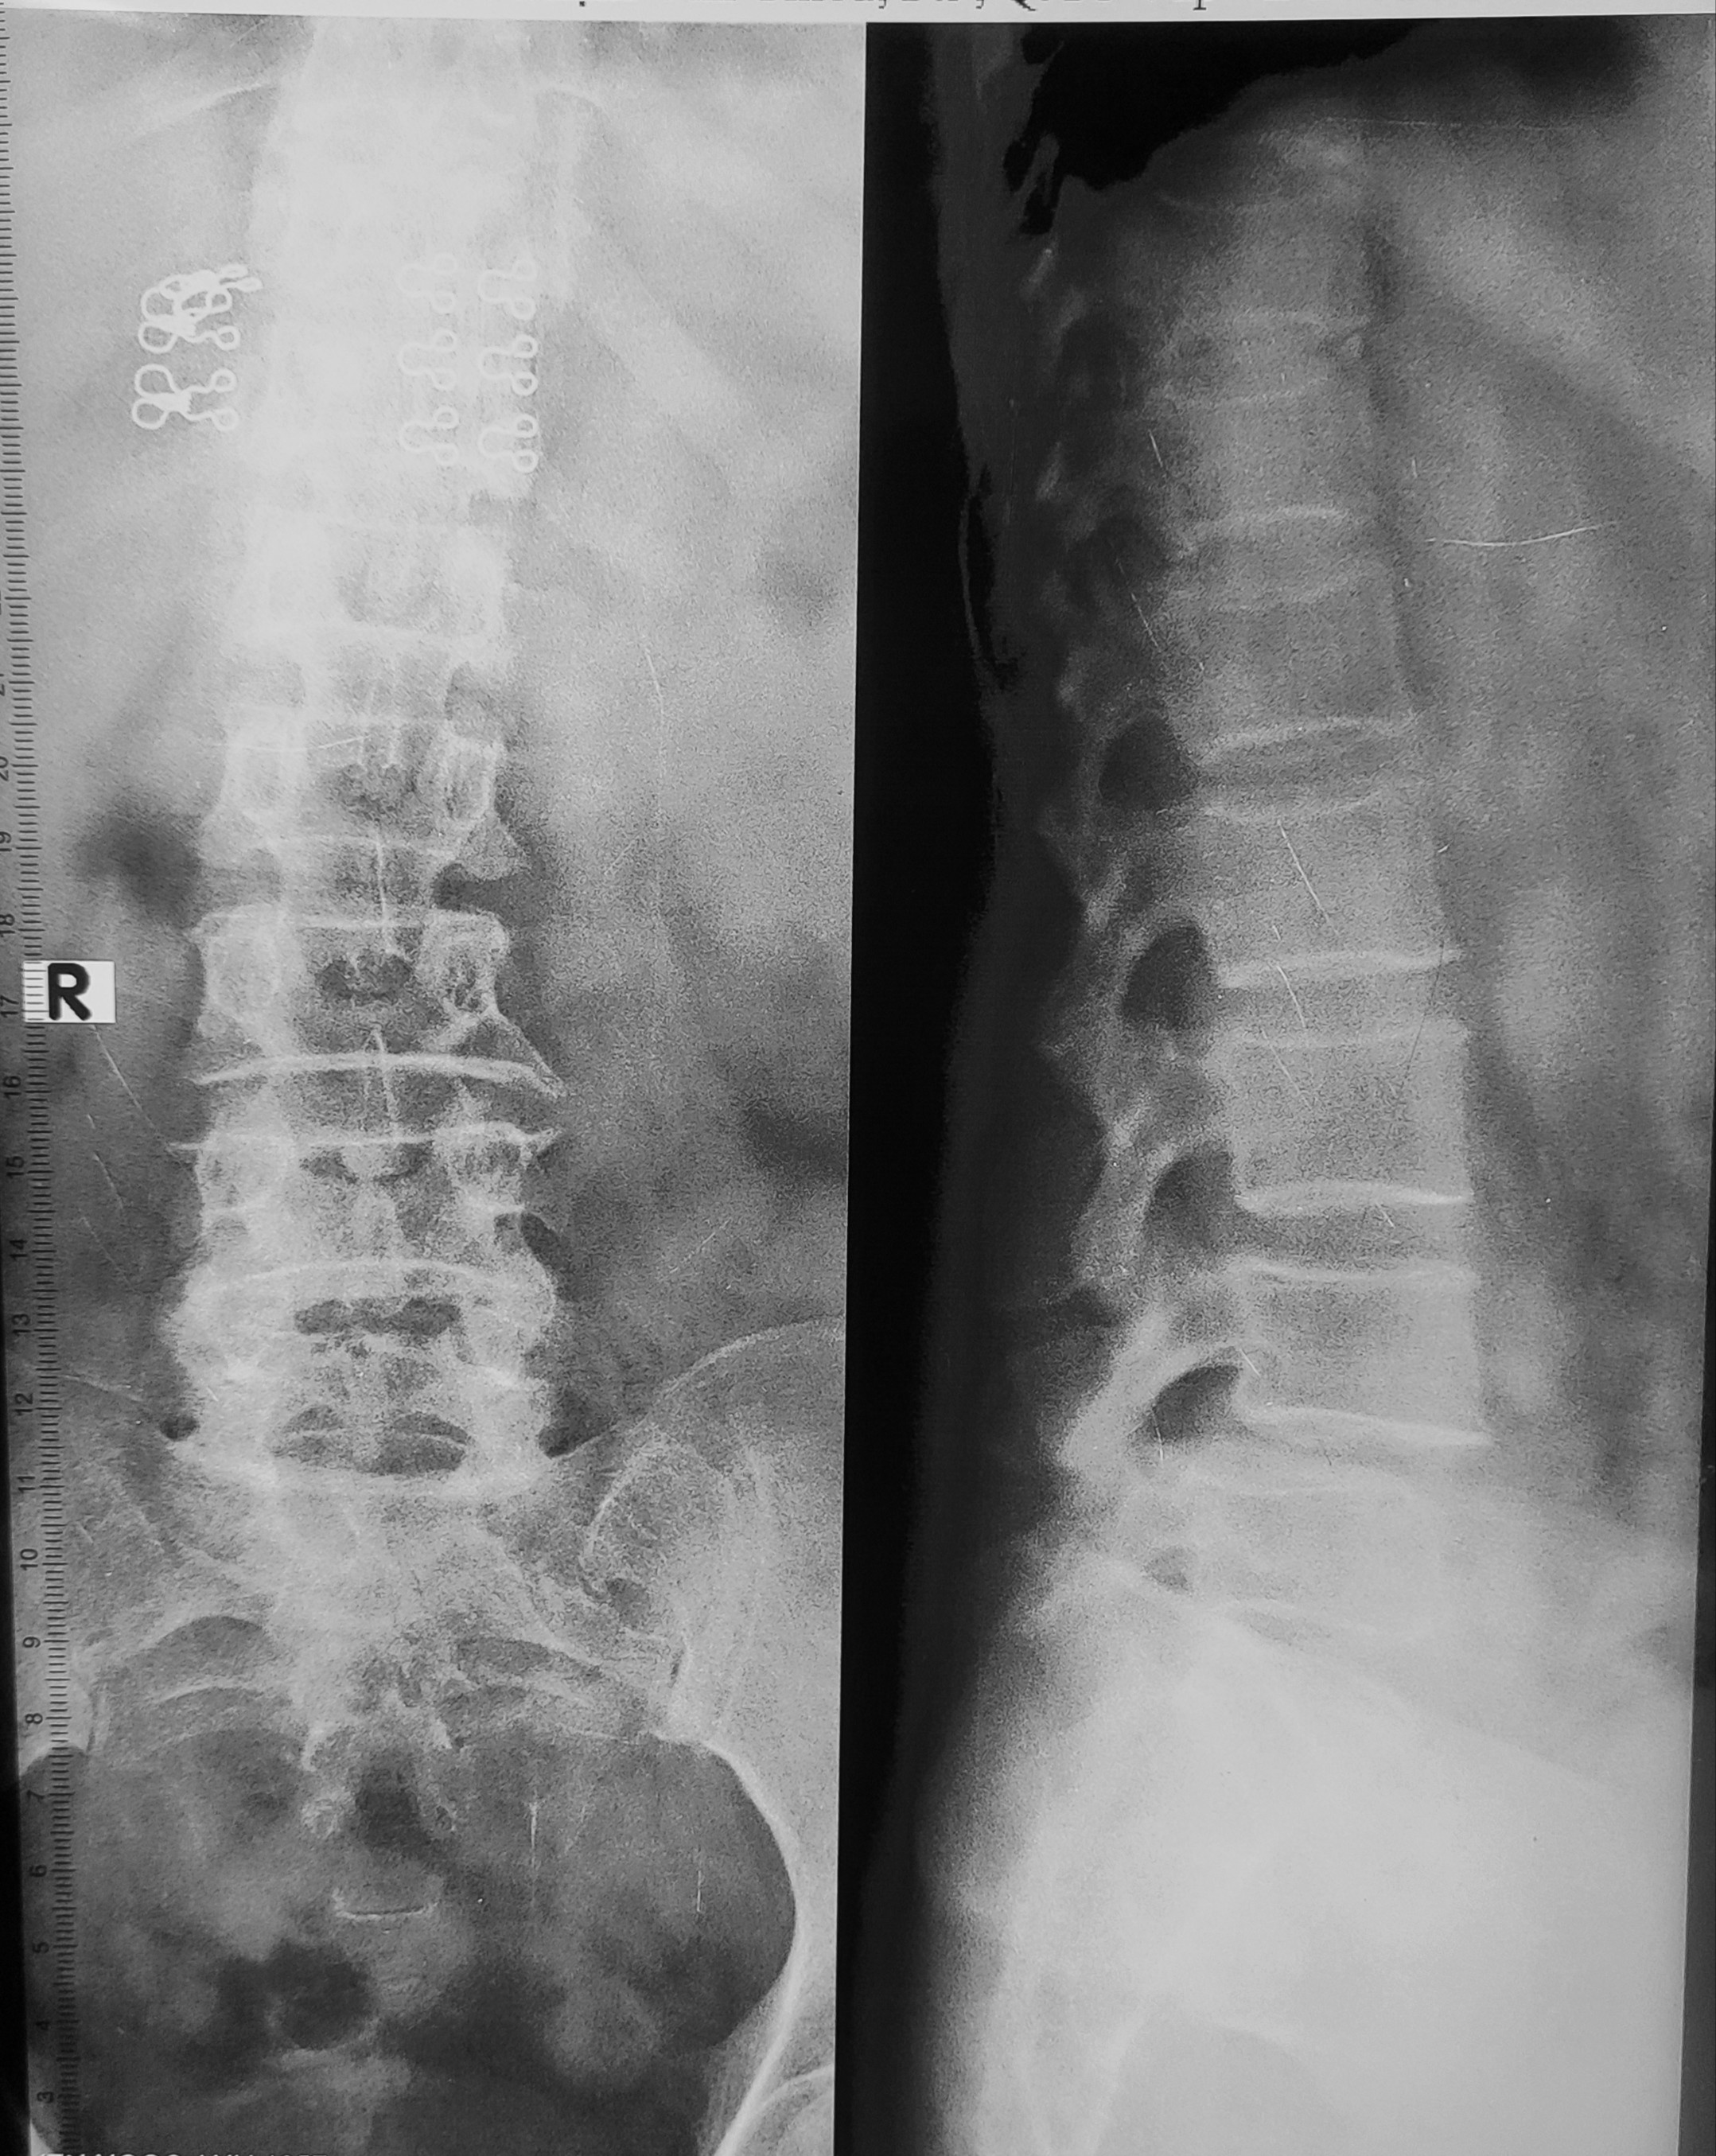

#xq Bn nữ 68t đau lưng, lan xuống mông, đùi, cẳng chân

Nhận định cá nhân: Trượt đốt sống L4 ra trước (độ 1). Hẹp khe đĩa đệm L4-L5, L5-S1. Gai xương L3-L4